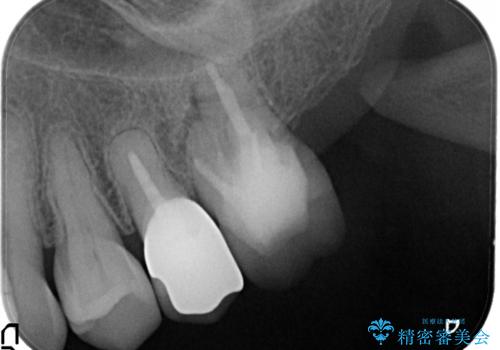

金属のかぶせ物をセラミックへ 根管治療からの再治療

左側の上下の奥歯に適合が悪く、レントゲン上でも根の治療が必要なところがありました。

再治療を行いました。

根管治療からの再治療を行ったことにより、治療期間が多少長くなりましたが、今後再治療の必要性があまりないような、精度の高い治療ができました。